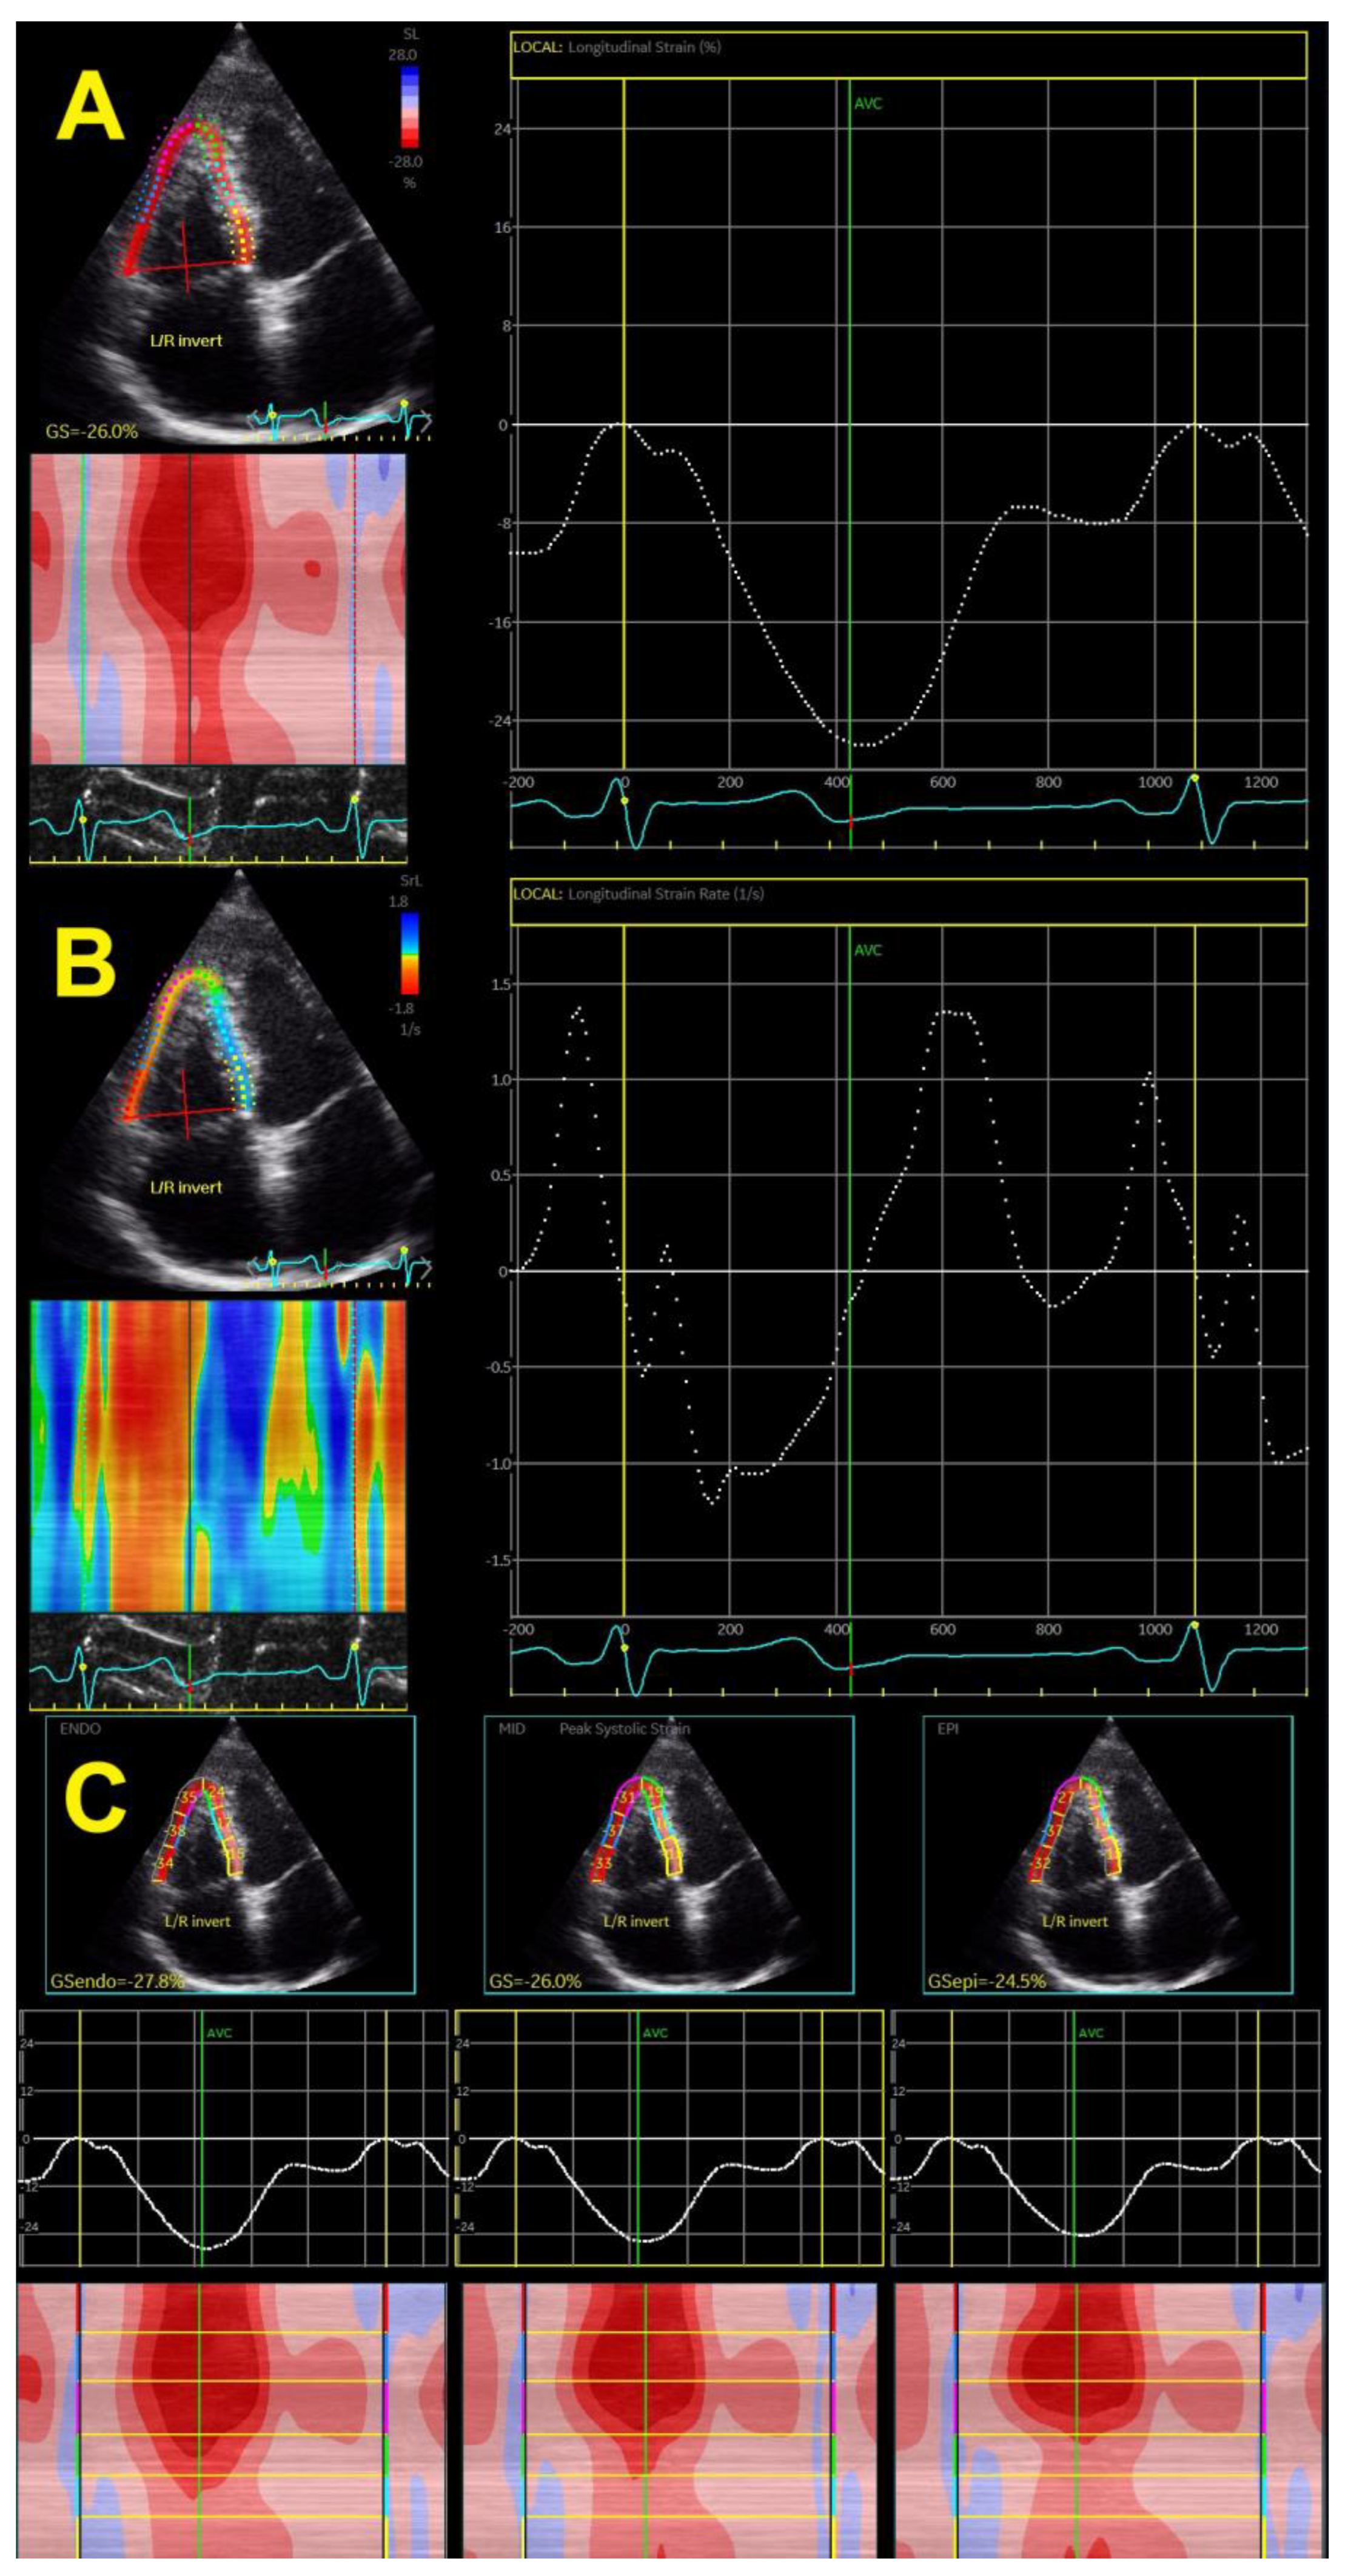

The speckle tracking-derived RV longitudinal strain has been the only method used in the last decade (Figure 3A), whereas the tissue-Doppler-derived strain has not been used for evaluation for a long time due to many limitations. This technique also provides a calculation of strain rates (systolic, early, and late diastolic strain rates) (Figure 3B), which is the speckle tracking equivalent to parameters obtained by tissue Doppler, giving data on systole and early and late diastole. Novel echocardiographic methods enable the assessment of epicardial and endocardial RV longitudinal strain rates (Figure 3C), which has also been used in the hypertensive population.

Figure 3.

Two-dimensional global right ventricular strain (A), right ventricular strain rate (B), and layer-specific strain—endocardial, mid-myocardial, and epicardial (C).

Early findings revealed that the free wall RV longitudinal strain was gradually reduced with systolic BP [27]. The same was reported for the early diastolic strain rate but not for late diastolic and systolic strain rates. Our study group showed that RV GLS and, particularly, free wall RV longitudinal strain were deteriorated in patients with different forms of hypertension, such as white-coat hypertension, masked hypertension, and nocturnal hypertension, but also in patients with high-normal BP [21,33,34,35,36]. Patients with unfavorable circadian BP patterns (non-dipping and reverse dipping) also have significantly lower values of RV longitudinal strain in comparison with dipping and extreme dipping BP patterns [33]. RV GLS also gradually reduced from hypertensive patients with normal geometry and concentric remodeling, across those with eccentric and dilated LVH, to those with concentric and concentric-dilated LVH [28].

Patients with comorbidities such as obesity, diabetes, and metabolic syndrome had worse RV GLS than patients with isolated hypertension [36,37,38,39], which shows that comorbidities have both additive and cumulative negative effects on RV mechanics. Studies also revealed that the RV endocardial layer was more impacted by arterial hypertension than the epicardial layer in hypertensive patients; this was also found in hypertensive patients with diabetes and obesity [34] and patients with white-coat or masked hypertension [33,34]. Systolic BP correlates well with layer-specific RV longitudinal strain, independent of other clinical and echocardiographic parameters [33,34,38].